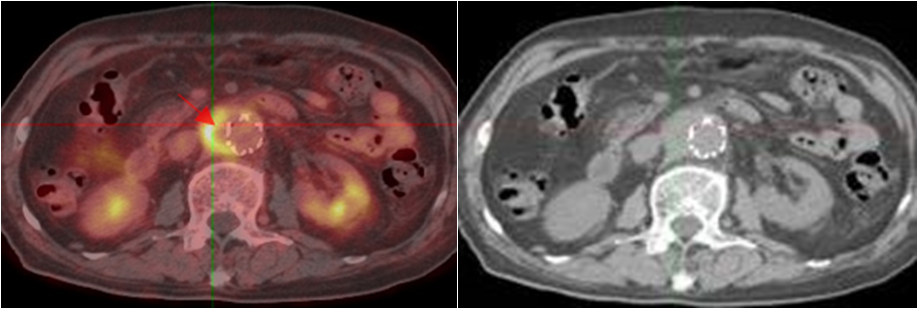

老年男性,反復(fù)發(fā)熱1年余;10年前因主動脈夾層行支架植入。PET/CT顯示支架周圍主動脈管壁增厚,代謝明顯增高,診斷為支架周圍感染。